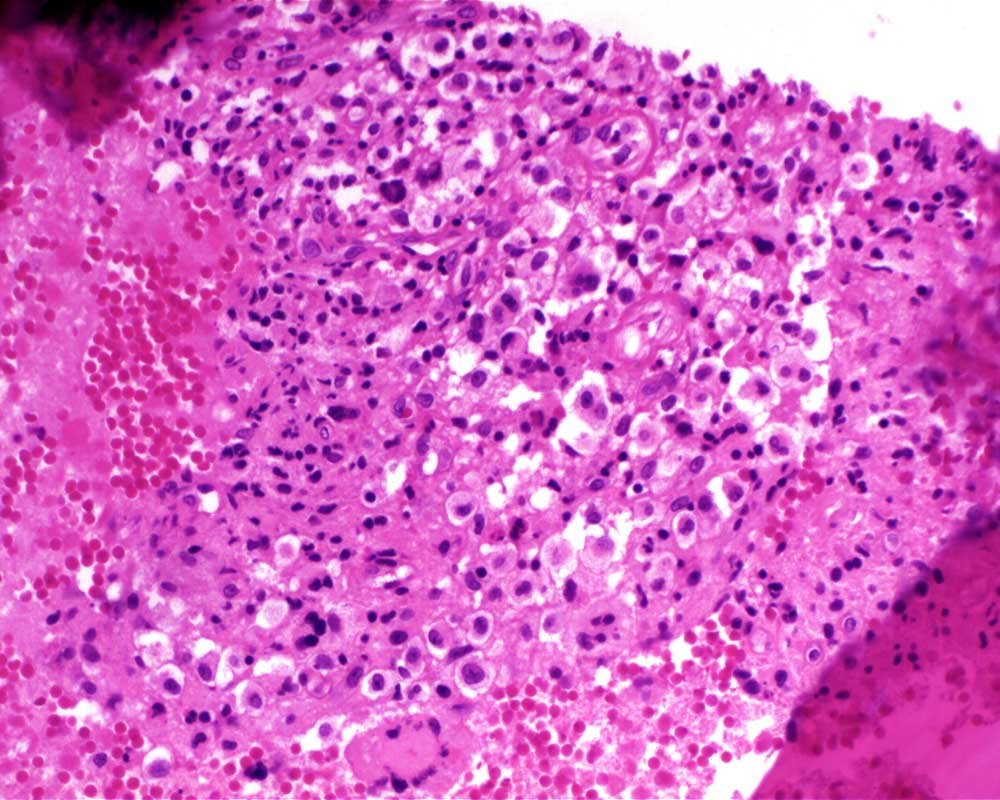

Case: FemurLesion

Final Diagnosis: